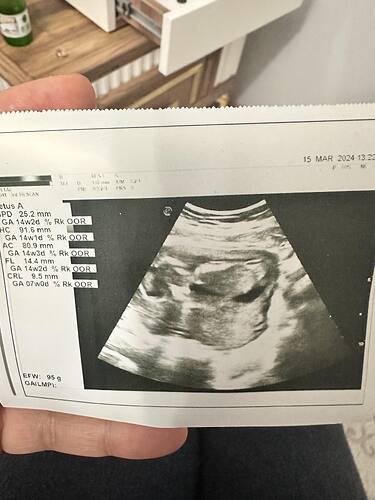

Senin tutunusu erkek

Eşim çok erkek istiyor, erkek olursa severim, kız olursa daha çok severim ama diyor ![]() sağlıklı olsunda hiç farketmez çok teşekkür ederim

![]() bi oğlum var bunu kız istiyorum Allah sağlıklı evlat versin en başta ama insan içinden geçen olsun istiyo tabiki

Cansuuu ikimizinkinin şekli aynı sanki, sence?

Ayy evet tekrar bakınca farkettim ![]()

Yuvarlak değil fasulye gibi daha çok ![]()

Bu da kuyruklu fasulyeye benziyor, erkek diyorum ![]()

Kız bebiş kesesi gibi ![]()

Çok net değil ama erkek bebiş kesesi gibi ![]()

Bence kız canim

Aynen fasulyeye benziyor bakalım tekrar gittiğimizde nasıl görünecek ![]()